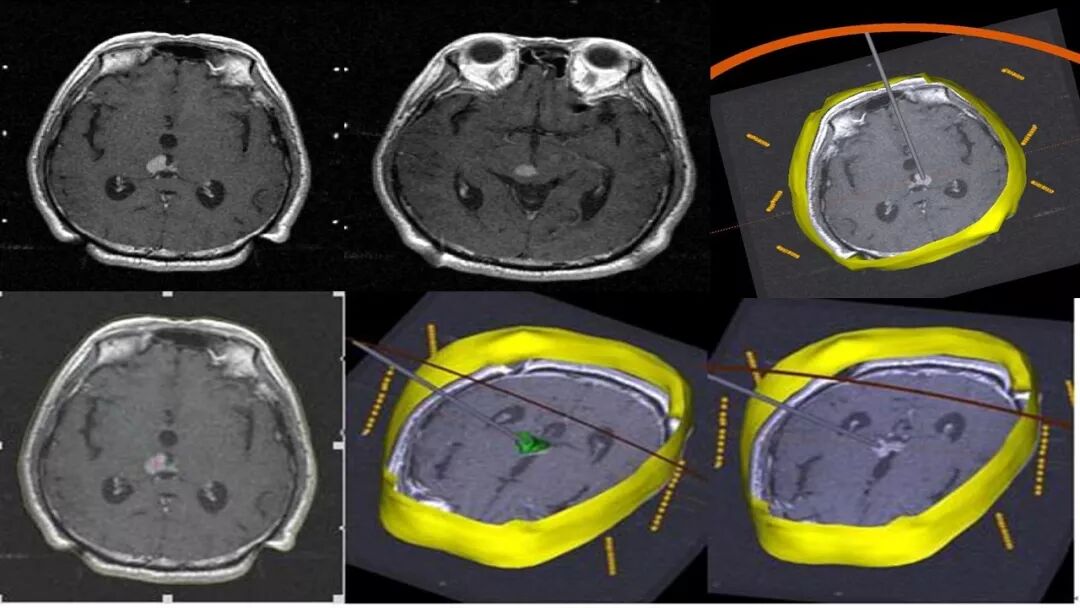

立体定向活检在脑干中线病变精准诊断中的作用

今天为大家带来的是中国人民解放军总医院第六医学中心(原中国人民解放军海军总医院)王亚明、于新、张剑宁带来的精彩课题分享:立体定向活检在脑干中线病变精准诊断中的作用,欢迎观看、阅读!